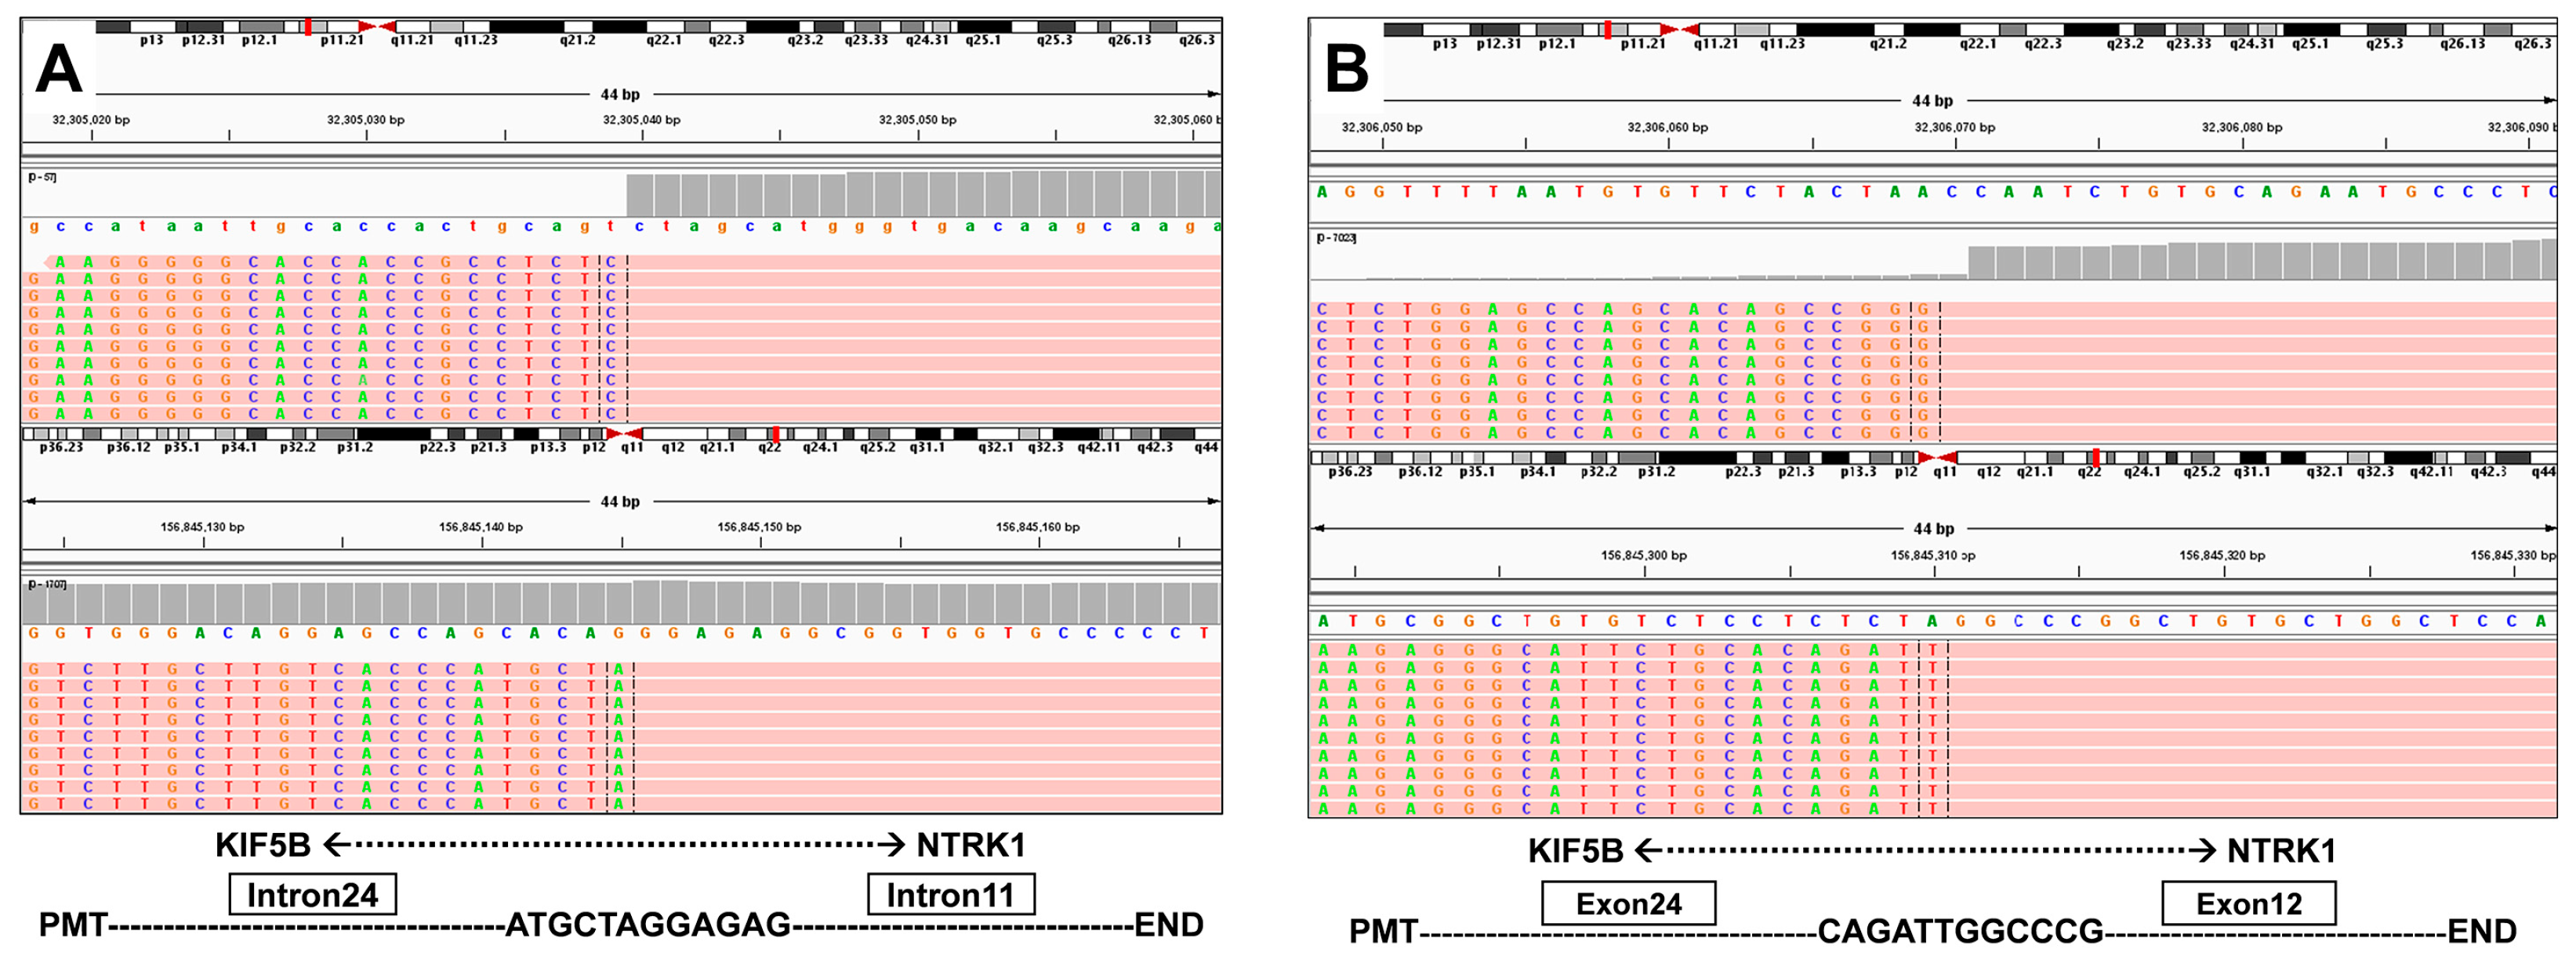

3.1. Case Description